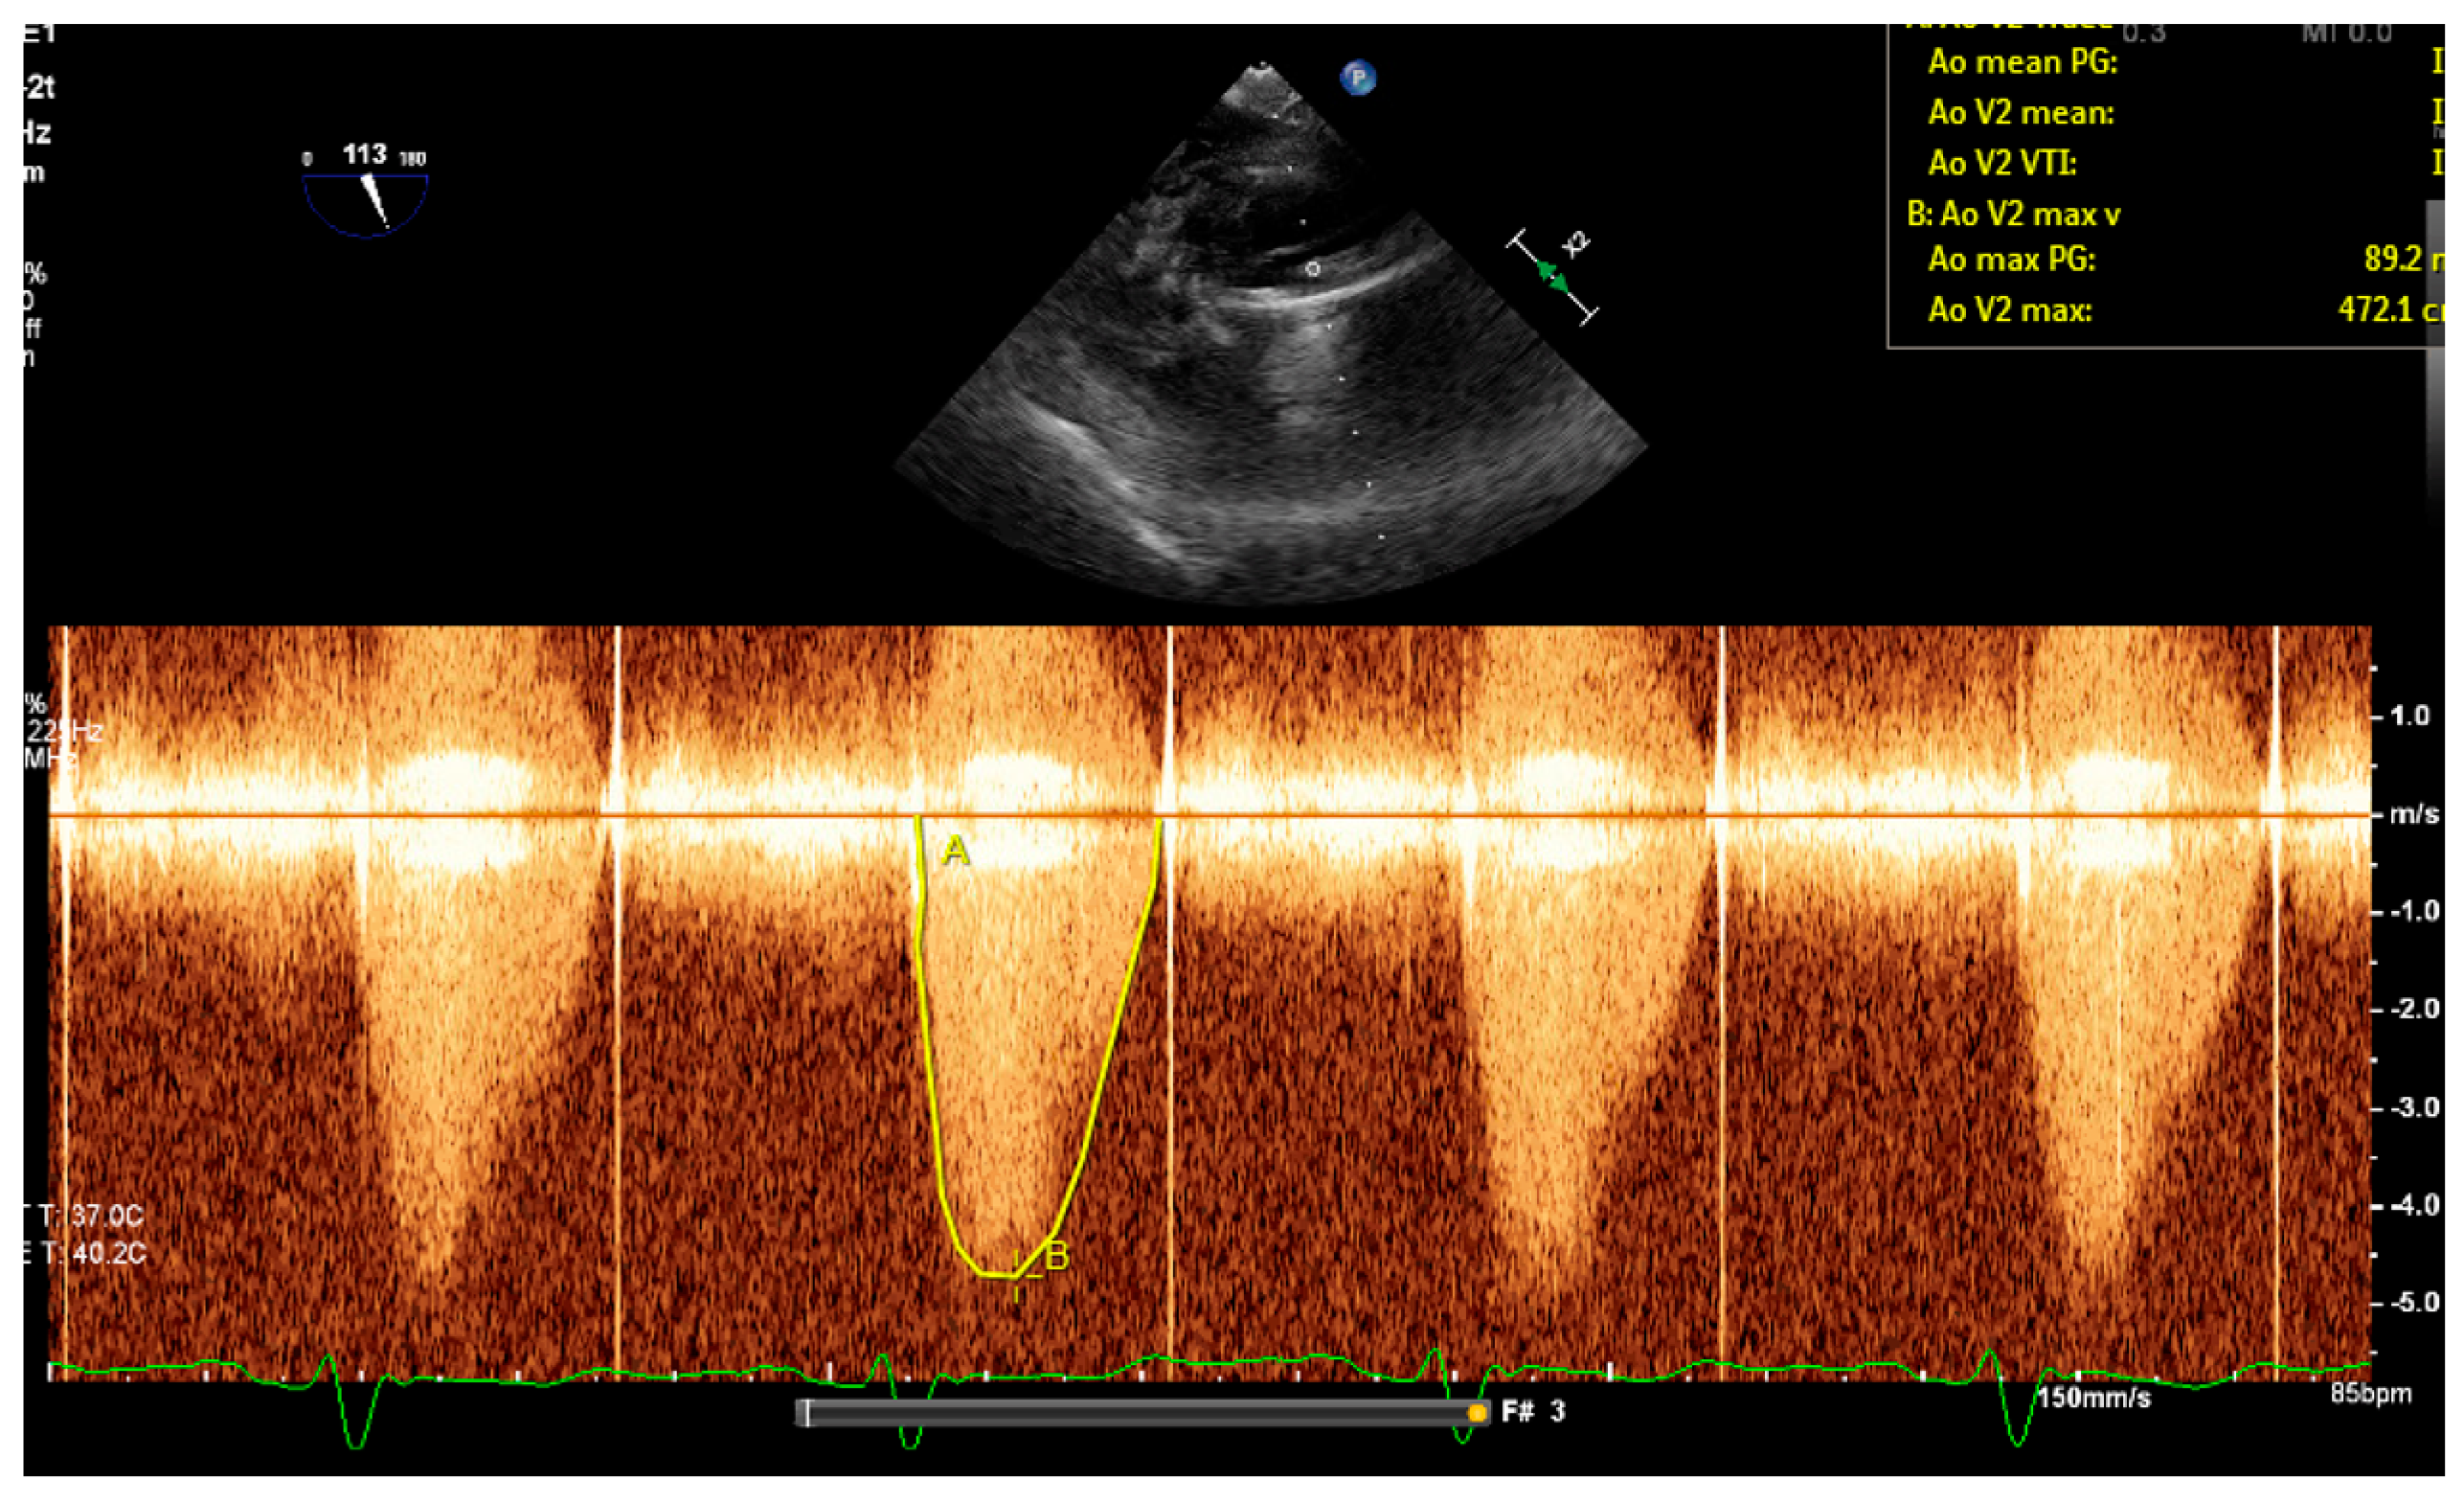

2. Patient Case